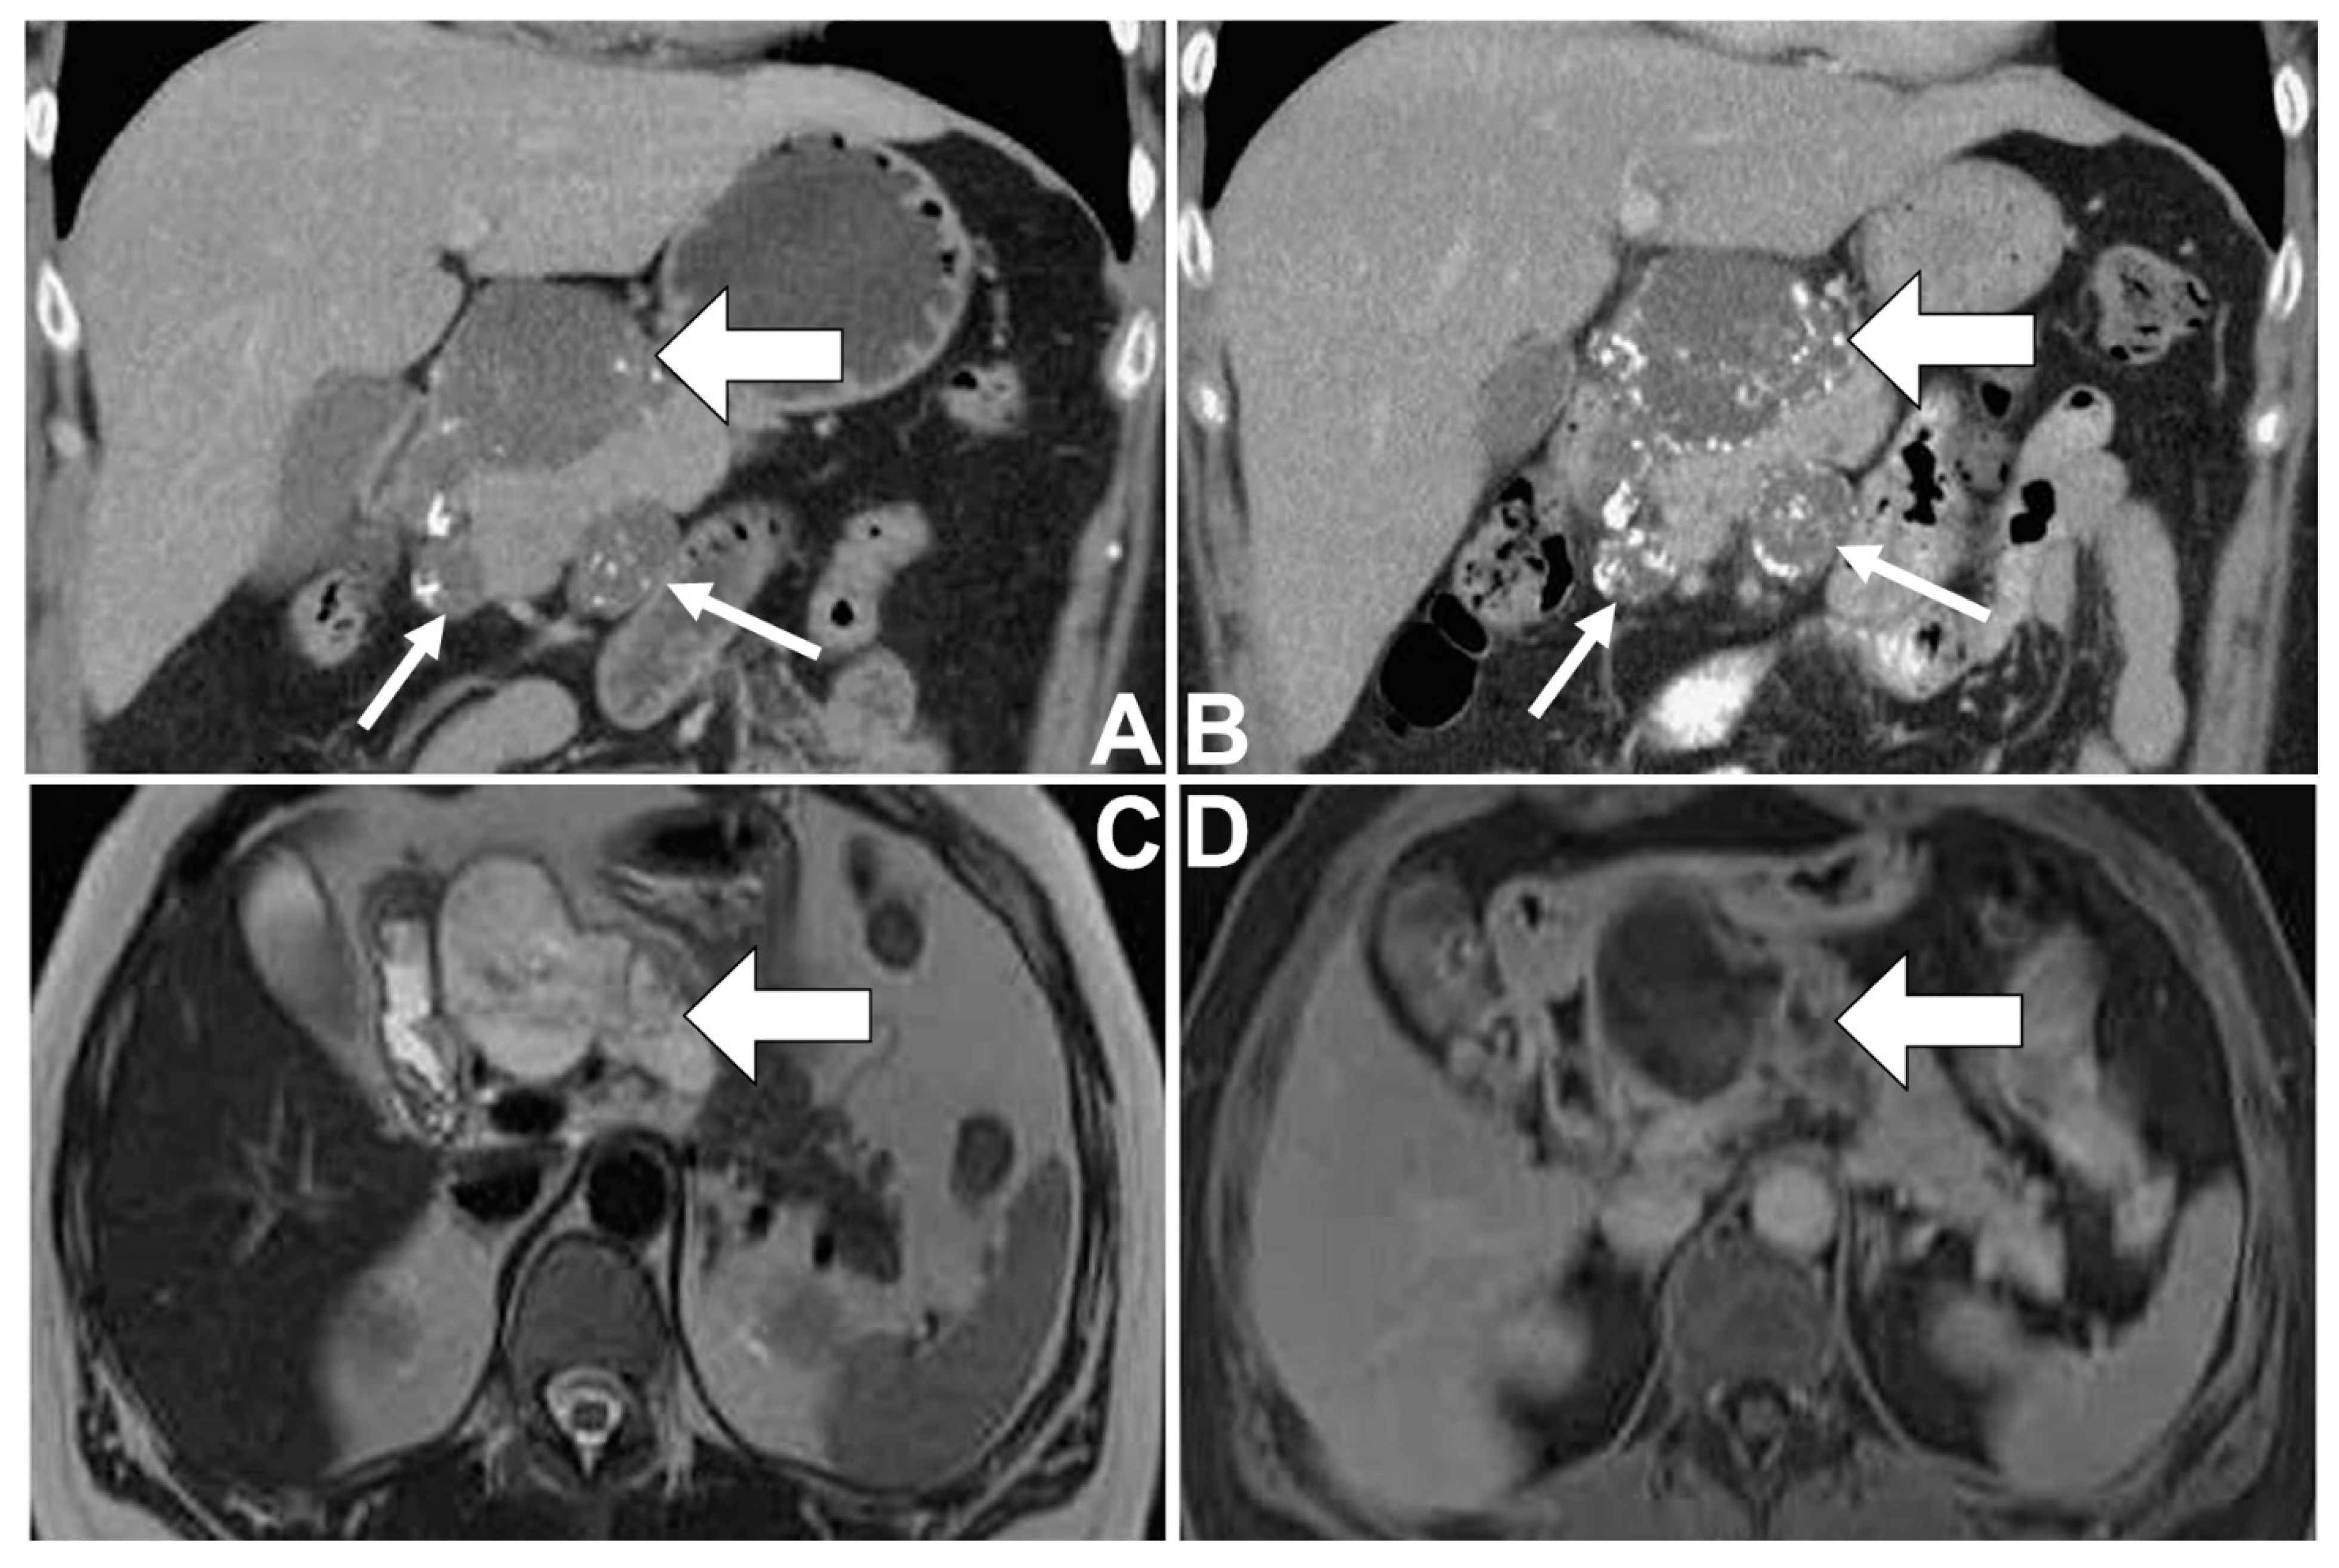

A 46-year-old female with a medical history of type II diabetes mellitus and idiopathic thrombocytopenia had regular follow-ups at the Department of Hemato-oncology at Taichung Veterans General Hospital, Taiwan. Due to her persistent thrombocytopenia in spite of therapy, imaging studies for an abdominal survey were arranged (Figure 1A–D). On computed tomography (CT) of the abdomen, a well-defined lobulated cystic mass was noted in the pancreatic head, where there was the presence of peripheral and internal calcifications and faint enhancement. Some smaller lesions having similar patterns were found around the mass abutting the pancreatic head. These imaging findings were suggestive of a cystic neoplasm of the pancreas, presumably malignant in nature with metastases involving lymph nodes. After that, the patient underwent magnetic resonance cholangiopancreatography (MRCP) for further evaluation. The cystic mass showed generally high signal intensity with some low signal foci and internal septa on T2-weighted images (T2WI). On dynamic imaging, the mass showed gradual enhancement at the periphery and internal septa. Some foci of faint enhancement were found within the cystic parts of the mass. In addition, possible metastases with enlarged lymph nodes were also found around the pancreatic head. Neither dilatation of the pancreatic duct nor communication between the mass and the pancreatic duct was found. A malignant mucinous cystic neoplasm of the pancreas with metastases involving lymph nodes was suspected, while IPMN was less likely radiologically.

Figure 1.

Colloid carcinoma of the pancreas in a 46-year-old woman. The coronal contrast-enhanced CT images at the time of initial presentation (A) and 10 months later (B) show a large well-defined lobulated cystic-appearing mass in the pancreatic head (thick arrow). Scattered peripheral and internal calcifications of the mass are noted. Lymphadenopathies (thin arrows) with similar imaging patterns of the mass are found around the pancreatic head. The follow-up image shows a slight increase in lesion size and calcifications. Marginal and septal enhancement and some intracystic enhancing foci are also found. The MRI at the time of initial presentation reveals a lobulated circumscribed hyperintense mass with some hypointense septa and foci on axial T2WI (C), as well as compatible CT enhancing patterns on axial T1WI gadolinium-enhanced delayed phase of MRI (D).